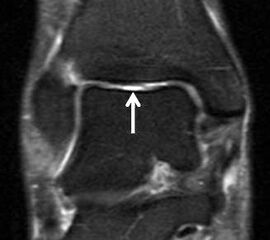

Physiologische Bandlücke (Pfeil)

Abbildung 9b

Eine Ursache der falschen Diagnose einer LFTA-Ruptur ist die Fehlinterpretation der physiologische Bandlücke zwischen dem LFTA und der vorderen Syndesmose als traumatischer Banddefekt (Abb. 9 b).

Die Interpretation pathologischer Veränderungen sollte daher immer multiplanar unter Verwendung möglichst dünner Schichtdicken und hoher Ortsauflösungen erfolgen, um Fehldiagnosen zu vermeiden.